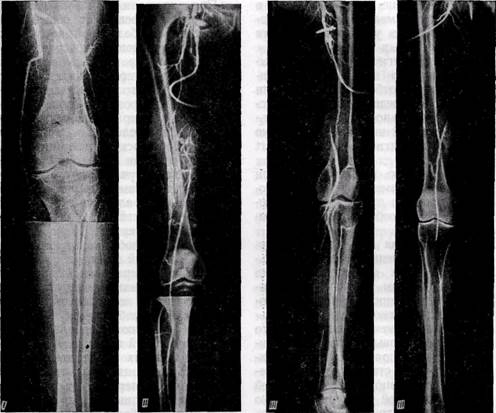

'Рис. 112.Артериограммы больных с различными типами окклюзии подколенно-берцово-

го сегмента